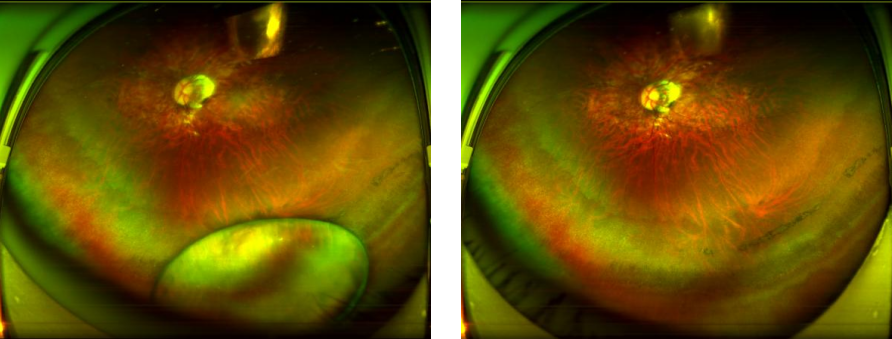

来自汕尾的王先生,一年前在家中突遭意外,被掉落的吊扇击伤左眼,出现眼红、畏光、流泪及外眦皮肤划伤出血。当地医院诊断“左眼晶状体脱位”并建议手术。为进一步治疗,他找到深圳华厦眼科医院院长、眼底眼外伤专家赵铁英教授。经检查,王先生除左眼晶状体脱位外,右眼并发性白内障、双眼高度近视视网膜病变(近视2000度)、双眼弱视,此时出现双眼1000多度的巨大屈光参差,他只能蒙住一个眼睛走路。

图:王先生术前(左)术后(右)眼底广角照相图

赵铁英院长经过详细的排查高度近视视网膜黄斑及周边情况后,交给朱远飞主任为其设计手术方案,并安全地实施了左眼玻璃体切除+脱位晶状体切除+眼内探查术;术后一个月对其右眼超高度近视并发性白内障,又进行白内障超声乳化摘除术+晶体张力环置入+人工晶体植入术。术后一个月复查,王先生双眼视力由术前0.05恢复到右眼 0.9,左眼 0.7的平衡状态,王先生摘掉了厚厚的眼镜,整个人年轻精神了很多,自言自语道:“我这还因祸得福了呢!以前戴着眼镜也没有这么清楚过!”不停对朱远飞主任、赵铁英院长及全体医护人员表达谢意。